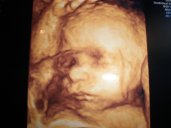

Pavli,gratulace k potvrzené holčičce,její fotečka je úžasná. Ty už jsi mi psala mejlíka,že? Byla jsi mezi prvními

Ahoj Brozanko,já už mám velký genetický UTZ za sebou,to jsem byla v té FN. Tohle jdu jen na 3D za 1000,- aby malá měla památku na dvd. Jdu k dr.Polákovi. S Maruškou jsem k němu chodila na screening a vše si nechala nahrát na dvd. Takže mám dvd ze 13.a pak z 21.tt,pěkné fotečky,jakože fakt fotky,ne na tom měkkým papíře jak z FN. A protože jsem měla dvě dvd,tak jsem si pak už jen ve 28.tt zašla pro 3D obličeje. :-) Jenže u něj ten první screening stojí 1400,-+se platí 100,- za tatínka,že se jde podívat. Pak 100,- za fotku,ale ta teda za to stojí. A 250,- myslím za dvd. Tak jsem tentokrát šla do FN,kde jsem měla screening zadarmo. Jenže dvd nemám,fotky jen na tom měkkým papíře a ještě nic moc. Tak jsme se s manželem dohodli,že si teda zaplatíme ten 3D,aby malá měla taky památku. Takže ve finále,jsme rovnou od začátku mohli chodit k němu,že :-D Ale co už teď..A jdeme tam na 19.hod.až. Jinak hříbky paráda teda!!!!! My byli v neděli a nasbírali jsme dva plný košíky a půlku tašky. Jenže my hříbky nepoznáme,tak museli jít s náma známí,abysme se neotrávili. :-D Dneska jedeme k ségře do Hradce Králové. Synoveček má zítra oslavu prvních narozenin,tak tam jedeme na víkend. Už se na ně všechny moc těším. :-) Jedeme až po obědě,až se manžel vyspí po noční. Naše Simča tam jela už včera vlakem s mým taťkou,aby pomohla ségře s dortem atd. Ona je taková naše pomocnice šikovná. Zvládne už sama uvařit celý oběd i upíct buchtu či bábovku. Nejlepší je,že ji to baví. :-) Brozanko,já Ti email určitě pošlu,ale až budu mít nějakou solidní fotku,ju!? ;-) :-D A Terezko,moc vám to sluší!!! Tak krásný den vám přeji,u nás teď vylezlo sluníčko. :-)

[621452] Jani krasne fotecky! Takove mám tez z 1. Tehu a vázne to stoji za to. Ty poplatky co za to chtěj kdyz maji ulz s 3D chápu! Můj Dr. mi říkal ze měli s kolegou zainvestovat o pul milionu víc aby to 3D bylo fakt kvalitni, ze za to co maji si nemůže účtovat. A byl to fakt rozdíl co jsme srovnali vysledky. Proto si jak vy zajdu samostatne na 3D :) krásný den ;)

Ahojda holky...fotečky 3D máte krásné, mě jí doktor tedka zkoušel dělat a kvuli placente vpředu to nebylo skoro vůbec vidět, tak jsme ji nakonec nechtěli...ještě uvidím, jak bude vypadat v 30tt, třeba se povede tam....